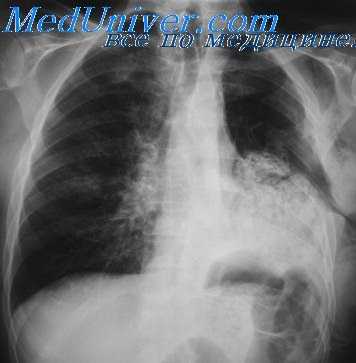

Традиционным при выполнении торакальных операций считается проведение однолегочной механической вентиляции легких с интубацией главного бронха (ГБ) в условиях миоплегии, со своими минусами, присущими искусственной вентиляции легких (ИВЛ) и миорелаксации. Анестезиологическое пособие в торакальной хирургии по праву признается одним из наиболее сложных из-за специфических трудностей, с которыми сталкивается анестезиолог [12]. Главное — легкое на стороне операции по абсолютным либо относительным показаниям должно быть временно выключено из вентиляции и коллабировано. Искусственная однолегочная вентиляция чревата развитием тяжелых расстройств гемодинамики и газообмена (гипоксемия) вследствие резкого увеличения внутрилегочного шунтирования и нарушения вентиляционно-перфузионных отношений, увеличением нагрузки и перегрузкой правого и левого отделов сердца, гипергидратацией легочного интерстиция, гиперкапнией и тяжелыми метаболическими расстройствами в виде дыхательного и метаболического ацидоза и т. д. [13—16]. Развивающиеся при этом патофизиологические процессы, их профилактика и коррекция являются основной проблемой торакальной анестезиологии. Проведение подобных операций с сохранением спонтанной вентиляции не создает особых проблем торакальному хирургу в виде «ограничения свободы действий», так как за счет атмосферного давления при открытии плевральной полости легкое в той или иной степени коллабируется (рис. 3).

Рис. 3. Эндофото. а — вид операционного поля без «выключения» легкого. Под сосуды корня легкого подведен сшивающий аппарат; б — прошивание сосудов. Легкое без признаков ателектаза.

Хотелось отметить, что, несмотря на неселективную интубацию после создания открытого пневмоторакса, под действием атмосферного давления легкое спадалось, его структуры хорошо визуализировались, что не мешало работе хирурга.